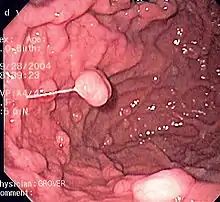

An endoscopy of a normal stomach of a healthy 65-year-old woman

Endoscopic image of a fundic gland polyp

A series of radiographs can be used to examine the stomach for various disorders. This will often include the use of a barium swallow. Another method of examination of the stomach, is the use of an endoscope. A gastric emptying study is considered the gold standard to assess the gastric emptying rate.[44]